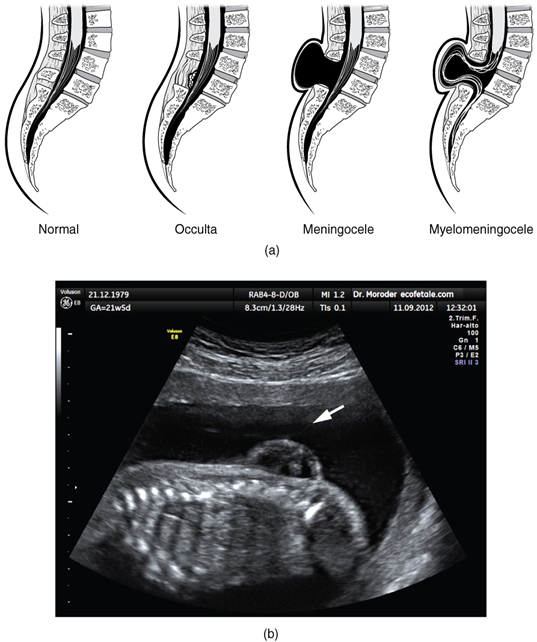

There are three classes of this disorder: occulta, meningocele, and myelomeningocele (Figure 13.6.4). The first type, spina bifida occulta, is the mildest because the vertebral bones do not fully surround the spinal cord, but the spinal cord itself is not affected. No functional differences may be noticed, which is what the word occulta means; it is hidden spina bifida. The other two types both involve the formation of a cyst—a fluid-filled sac of the connective tissues that cover the spinal cord called the meninges. “Meningocele” means that the meninges protrude through the spinal column, but nerves may not be involved, and few symptoms are present, though complications may arise later in life. “Myelomeningocele” means that the meninges protrude, and spinal nerves are involved, and therefore severe neurological symptoms can be present.

Spinal bifida

Figure 13.6.4. Spinal bifida. (a) Spina bifida is a birth defect of the spinal cord caused when the neural tube does not completely close, but the rest of development continues. The result is the emergence of meninges and neural tissue through the vertebral column. (b) Foetal myelomeningocele is evident in this ultrasound taken at 21 weeks.